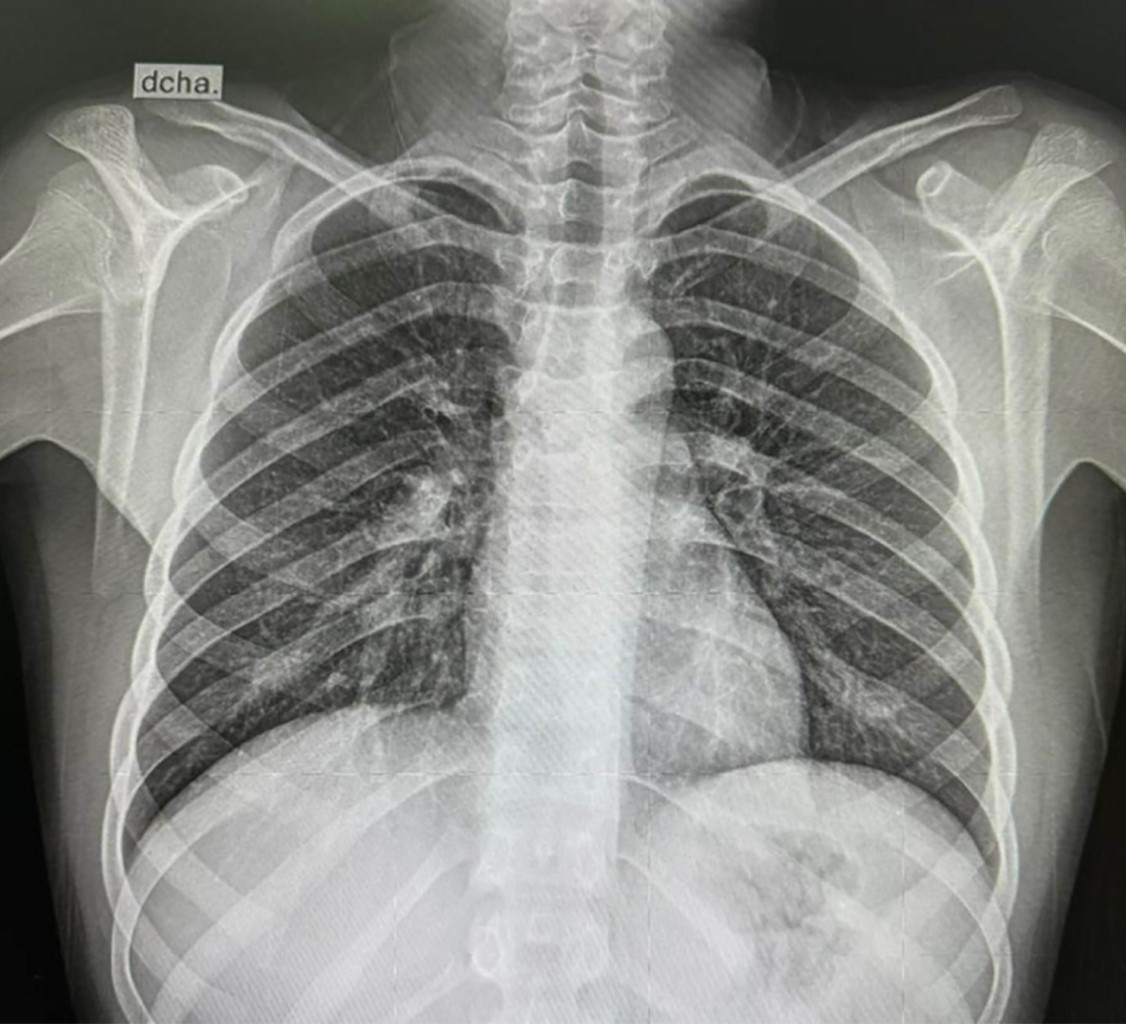

Figure 1

Figure 2

Figure 3